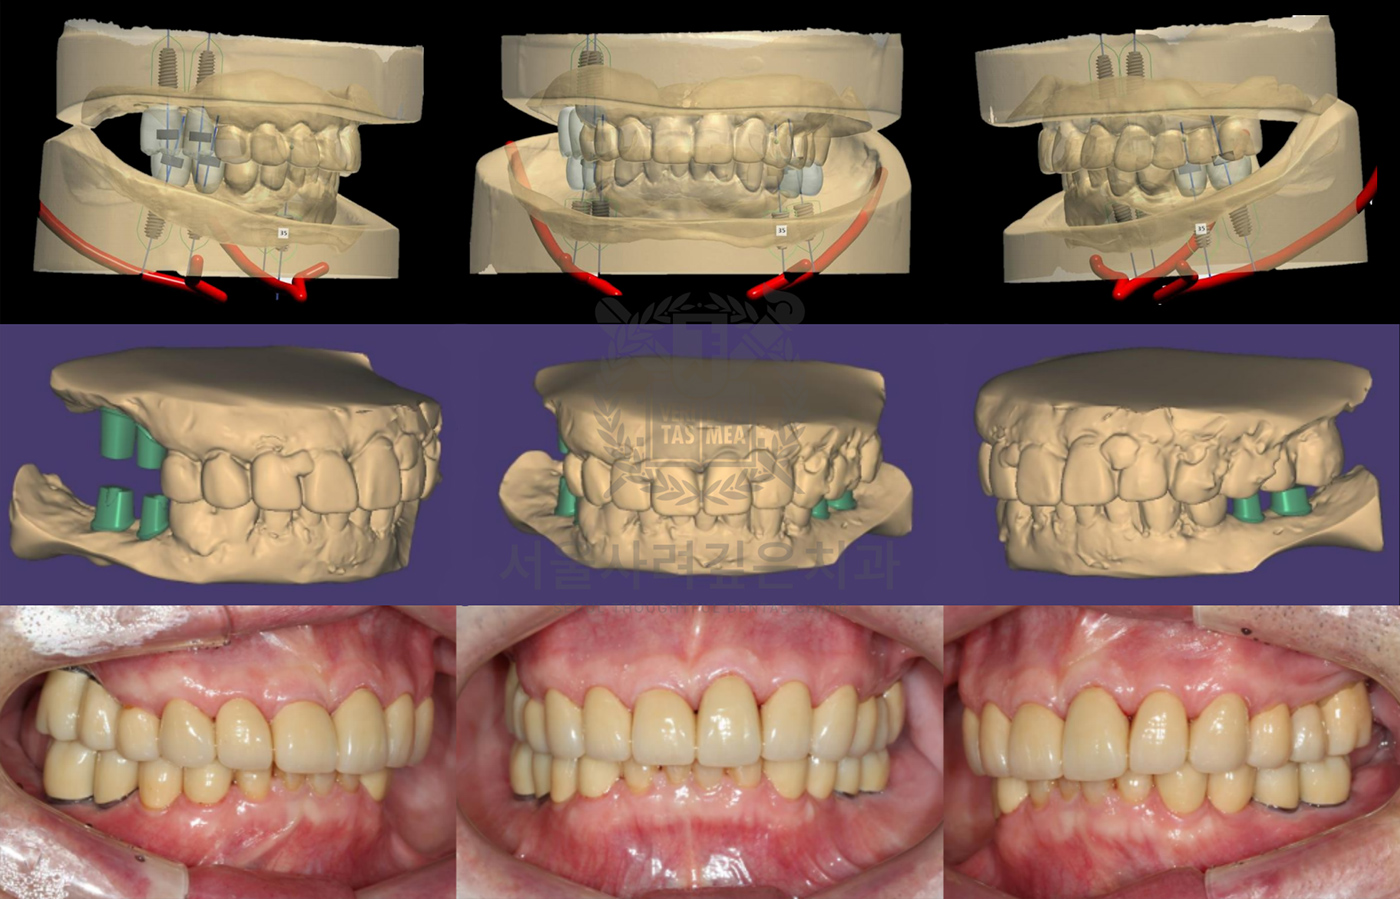

보철까지 고려한 디지털 임플란트

임플란트 클리닉

임플란트에 시술에 있어 가장 중요한 것은

‘최종 보철물의 위치와 형태’입니다.

서울사려깊은치과에서는 임플란트의 최종 보철물을 먼저 설계하고,

그에 맞춰 임플란트의 식립 위치와 각도를 결정하는 것을

원칙으로 합니다.

-

3D CT와 구강 스캐너를 통한

정밀한 시뮬레이션

사전에 제작된 수술 가이드를 통한

네비게이션 가이드 수술

디지털 네비게이션

임플란트

디지털 기술을 이용해 정교한 3D 모델을 만들고

정확한 위치에 임플란트를 식립하여

높은 정밀도로 맞춤형 치료를 제공합니다.

보철 중심의

임플란트 설계

최종 보철물(크라운, 브릿지 등)의

위치와 형태를 먼저 설계한 뒤,

그에 맞춘 최적의 위치에 임플란트를 정확히 심는

탑다운 치료 계획(Top-Down Planning)을 적용합니다.